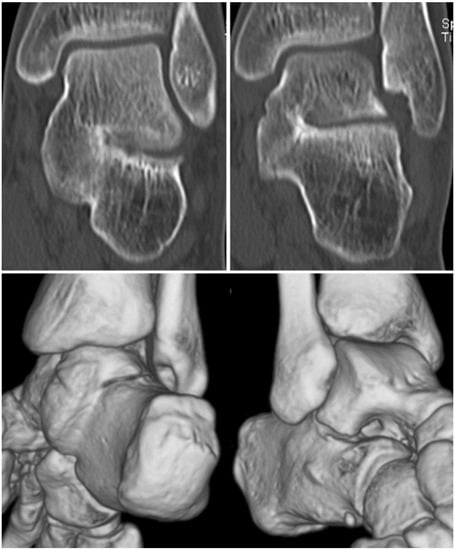

A tarsal coalition is an abnormal connection of the tarsal bones of the foot [1,2]. This bridging can be fibrous, cartilaginous, or bony in origin, and most often involves the talocalcaneal (Figure 1) or calcaneonavicular joints (Figure 2) [1,3]. Other more rare tarsal coalitions include talonavicular, cubonavicular, naviculocunieform, and calcaneocuboid [3,4]. Congenital coalitions occur in an autosomal dominant fashion from a failure of early mesenchymal differentiation [2,4]. Recent research has identified a proline to arginine mutation in the fibroblast growth factor receptor 3 (FGFR3) gene in association with these malformations [5]. While tarsal coalitions can be associated with other congenital disorders such as Apert syndrome or Nievergelt-Pearlman syndrome, it is more common for these abnormalities to be isolated occurrences [6,7,8,9]. Acquired tarsal coalitions can be caused by degenerative joint disease, inflammatory arthritis, infectious sequelae, or clubfoot deformities [1,4,6].

Figure 1. Talocalcaneal coalition, as viewed from two coronal CT sections (upper images) and three-dimensional (3D) reconstruction (lower image). Abnormal bony coalition is noted at the medial aspect of the posterior facet of the subtalar joint [10] (Borrowed using Creative Commons licensing).